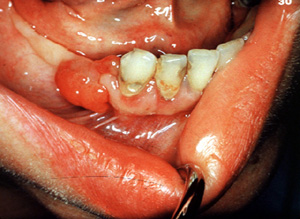

Aquí hay otro ejemplo típico ocurriendo en el mucosa edéntula. Incluso la irritación más ligera puede causar  hemorragia. Un granuloma  piógeno  pueden crecer rápidamente y pueden simular un tumor maligno; obviamente, el diagnóstico preciso requiere de la biopsia.